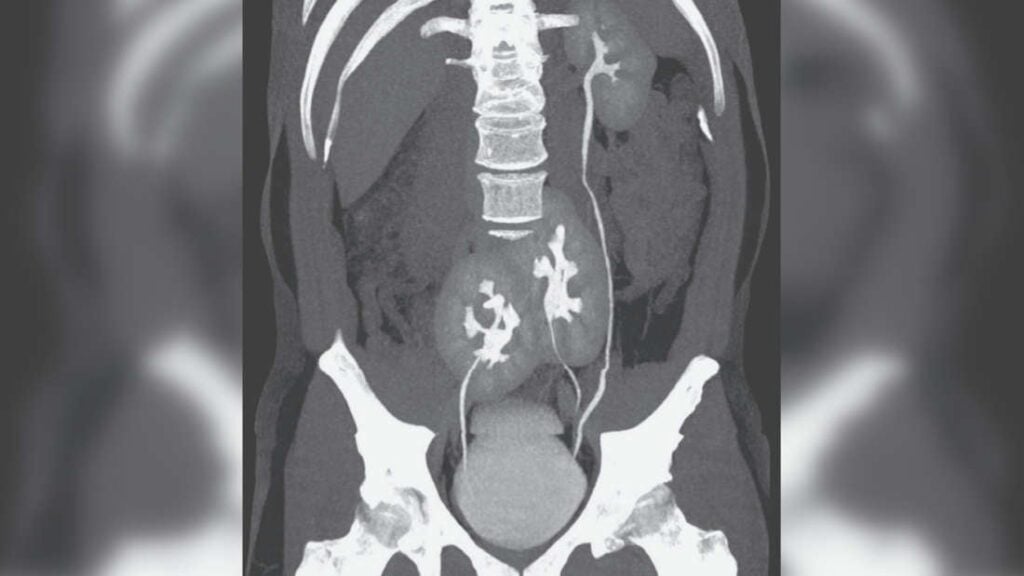

El caso apareció publicado en New England Journal of Medicine (NEJM) la semana pasada. Un hombre de 38 años visitó un hospital en la ciudad de São Paulo debido a un fuerte dolor lumbar. La posterior tomografía computarizada (TC) reveló que el paciente tenía tres riñones en su abdomen: un riñón izquierdo de apariencia normal,…